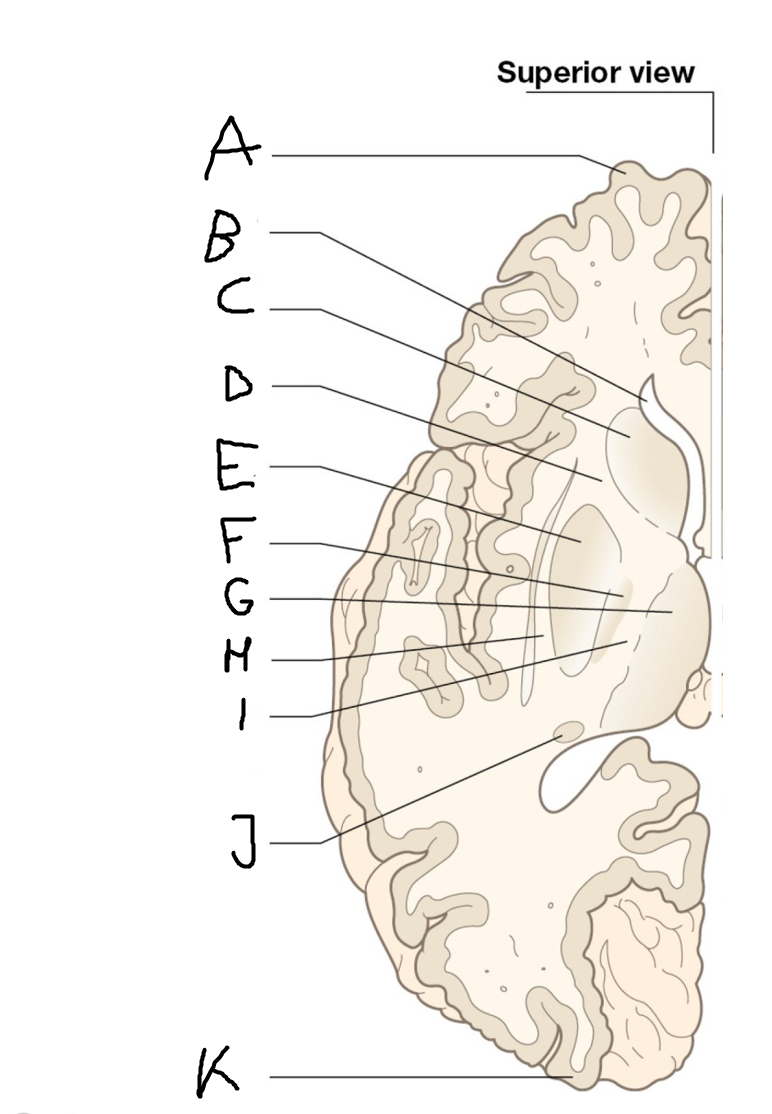

internal capsule (posterior limb)

B

anterior horn of lateral ventricle

C

head of caudate nucleus

D

internal capsule (anterior limb)

E

putamen

F

globus pallidus

G

Thalamus

H

External capsule

I

internal capsule (posterior limb)

J

tail of caudate nucleus